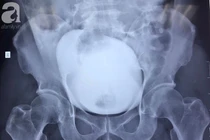

![]() |

| Ảnh minh họa: Internet |